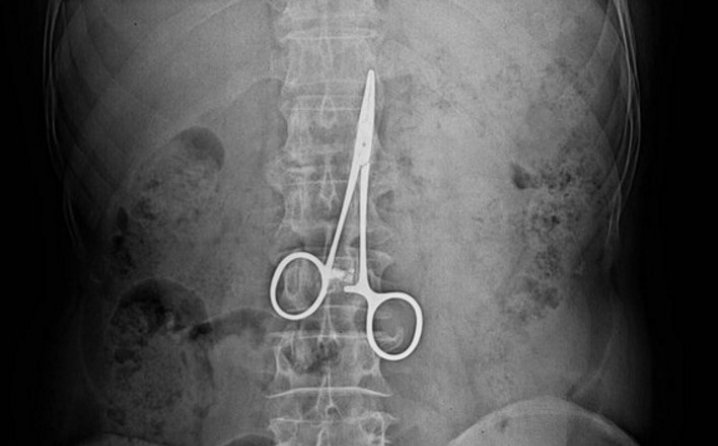

– Imao sam nesnošljiv konstantan kašalj, kojeg se nikako nisam mogao riješiti. Na kraju sam otišao na CT pluća i doživio šok. Na snimci su se vidjele makaze duge 12 centimetara! To su u biti makaze koje se na operacijama koriste za zaustavljanje krvarenja, mislim da im je stručni naziv ‘pean’. One su u biti malo podigle pluća s jedne strane i to mi je izazivalo stalni kašalj, ispričao je tada Papac.

Papac je u novembru 2012. primljen u SKB Mostar gdje mu je izvršen operativni zahvat kada je utvrđeno da se nalazi vrlo lošem zdravstvenom stanju. Nakon detaljnog pregleda ustanovljeno da mu je jedno plućno krilo uvećano, a snimak je pokazao da se u tijelu tužitelja nalaze makaze. I to u debelom crijevu! Makaze su u tijelu tužitelja ostale prilikom operativnog zahvata koji je izveden u SKB Mostar u augustu 2003. godine. Papac je tokom postupka izjavio da je nakon prvog operativnog zahvata imao ogromne bolove zbog čega je kod istog došlo do znatnog umanjenja životne aktivnosti. Tek pregledom i operativnim zahvatom 2012. godine ustanovljeno je da su greškom ljekara u debelom crijevu Alena Papca ostale makaze koje je nosio 9 godina.

Iz nalaza je vidljivo da je ostavljeni hirurški instrument „putovao“ kroz tijelo tužitelja devet godina i to kroz tanko crijevo, a potom kroz debelo crijevo, gdje se zaustavio na poprečnom debelom crijevu i izazvao oštećenje zida debelog crijeva, radi čega se zaustavio gdje je i pronađen. Sve je to uzrokovalo jake bolove, te izuzetno loše psihičko stanje Alena Papca.